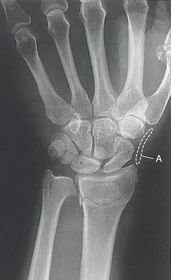

Ulnar Deviation